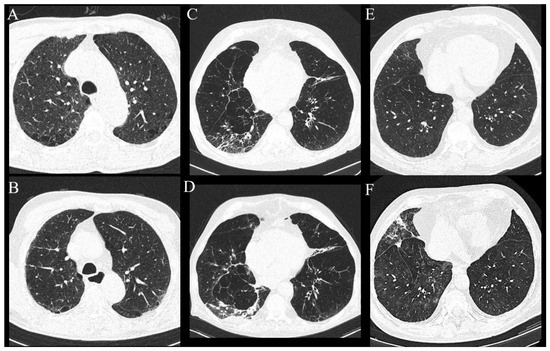

Figure 5.

Axial MSCT scans of lung parenchyma demonstrating progression of existing and newly developed findings in HNSCC patients after cancer treatment. (A,B) Patient had subpleural non-fibrotic ILA subcategory in the lower lung zones, but middle lung zones were not involved (as shown on the picture), and only paraseptal emphysema was visible. In the follow-up period, the patient demonstrated newly developed subpleural reticulations with zones of GGO, which was characterized as probable UIP pattern. (C,D) Same patient with progression of subpleural fibrotic ILAs manifested as fibrous consolidations in the right lower lobe and newly developed subpleural reticulations which persisted on subsequent scans. (E,F) Patient with progression of subpleural non-fibrotic ILA now seen as fibrotic consolidations, reticulations and areas of GGO. Patient had centrilobular nodules diffusely arranged throughout lung parenchyma, which became more prominent.

The follow-up lung MSCT scans were available for 65 out of 113 patients, of which 11 were patients with ILAs (11 of a total number of 15 with ILAs), within a median of 24 months (Q1-Q3 13–32 months) from the baseline lung MSCT performed. Progression of existing ILA changes was described in three patients (27.27%). The first patient, after having surgical resection and adjuvant chemoradiotherapy, developed new non-emphysematous cysts and more prominent subpleural reticulations in all lung zones with areas of GGO and was characterized as a possible usual interstitial pneumonia (UIP) pattern. The second and third patients, after having surgical resection followed by adjuvant radiotherapy, developed fibrous consolidations with GGO areas and newly developed reticulations (Figure 5). All patients had subpleural ILAs in the lower lung zones.